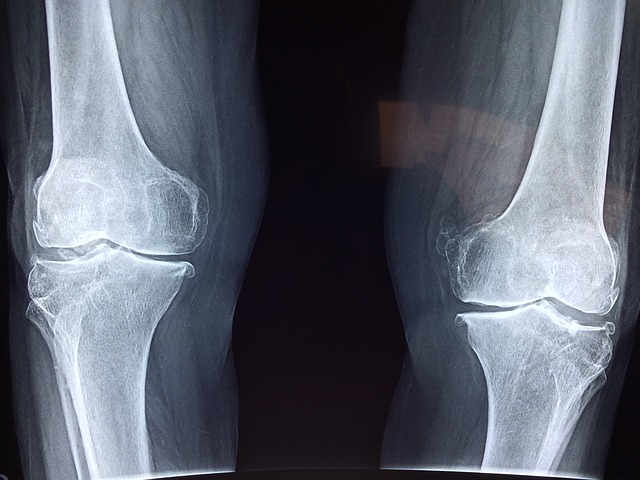

뼈는 서로 연결되어 관절을 형성하며, 이 관절은 운동 가능성을 증가시킵니다. 예를 들어, 팔꿈치 관절은 상완골, 요골 및 척골이 만나 이루어지며, 자유로운 팔의 움직임을 가능하게 합니다.

뼈는 주로 몸체의 하중을 지지하는 역할을 하며, 이 과정에서 압력을 경험합니다. 뼈는 건강한 상태에서 이러한 압력을 효과적으로 견디지만, 지나친 압력이 가해질 경우 골절과 같은 부상을 초래할 수 있습니다. 특히 하중이 집중되는 부위에서는 골절이 자주 발생하는데, 자주 골절되는 부위로는 팔, 다리, 갈비뼈, 그리고 쇄골이 있습니다.